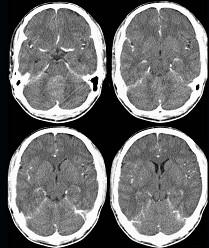

问题 男,16岁,头痛、呕吐10天,CT检查如图所示,最可能的诊断为()

选项 A.脑膜瘤 B.髓母细胞瘤 C.室管膜瘤 D.脑血管瘤 E.血管母细胞瘤

答案 B